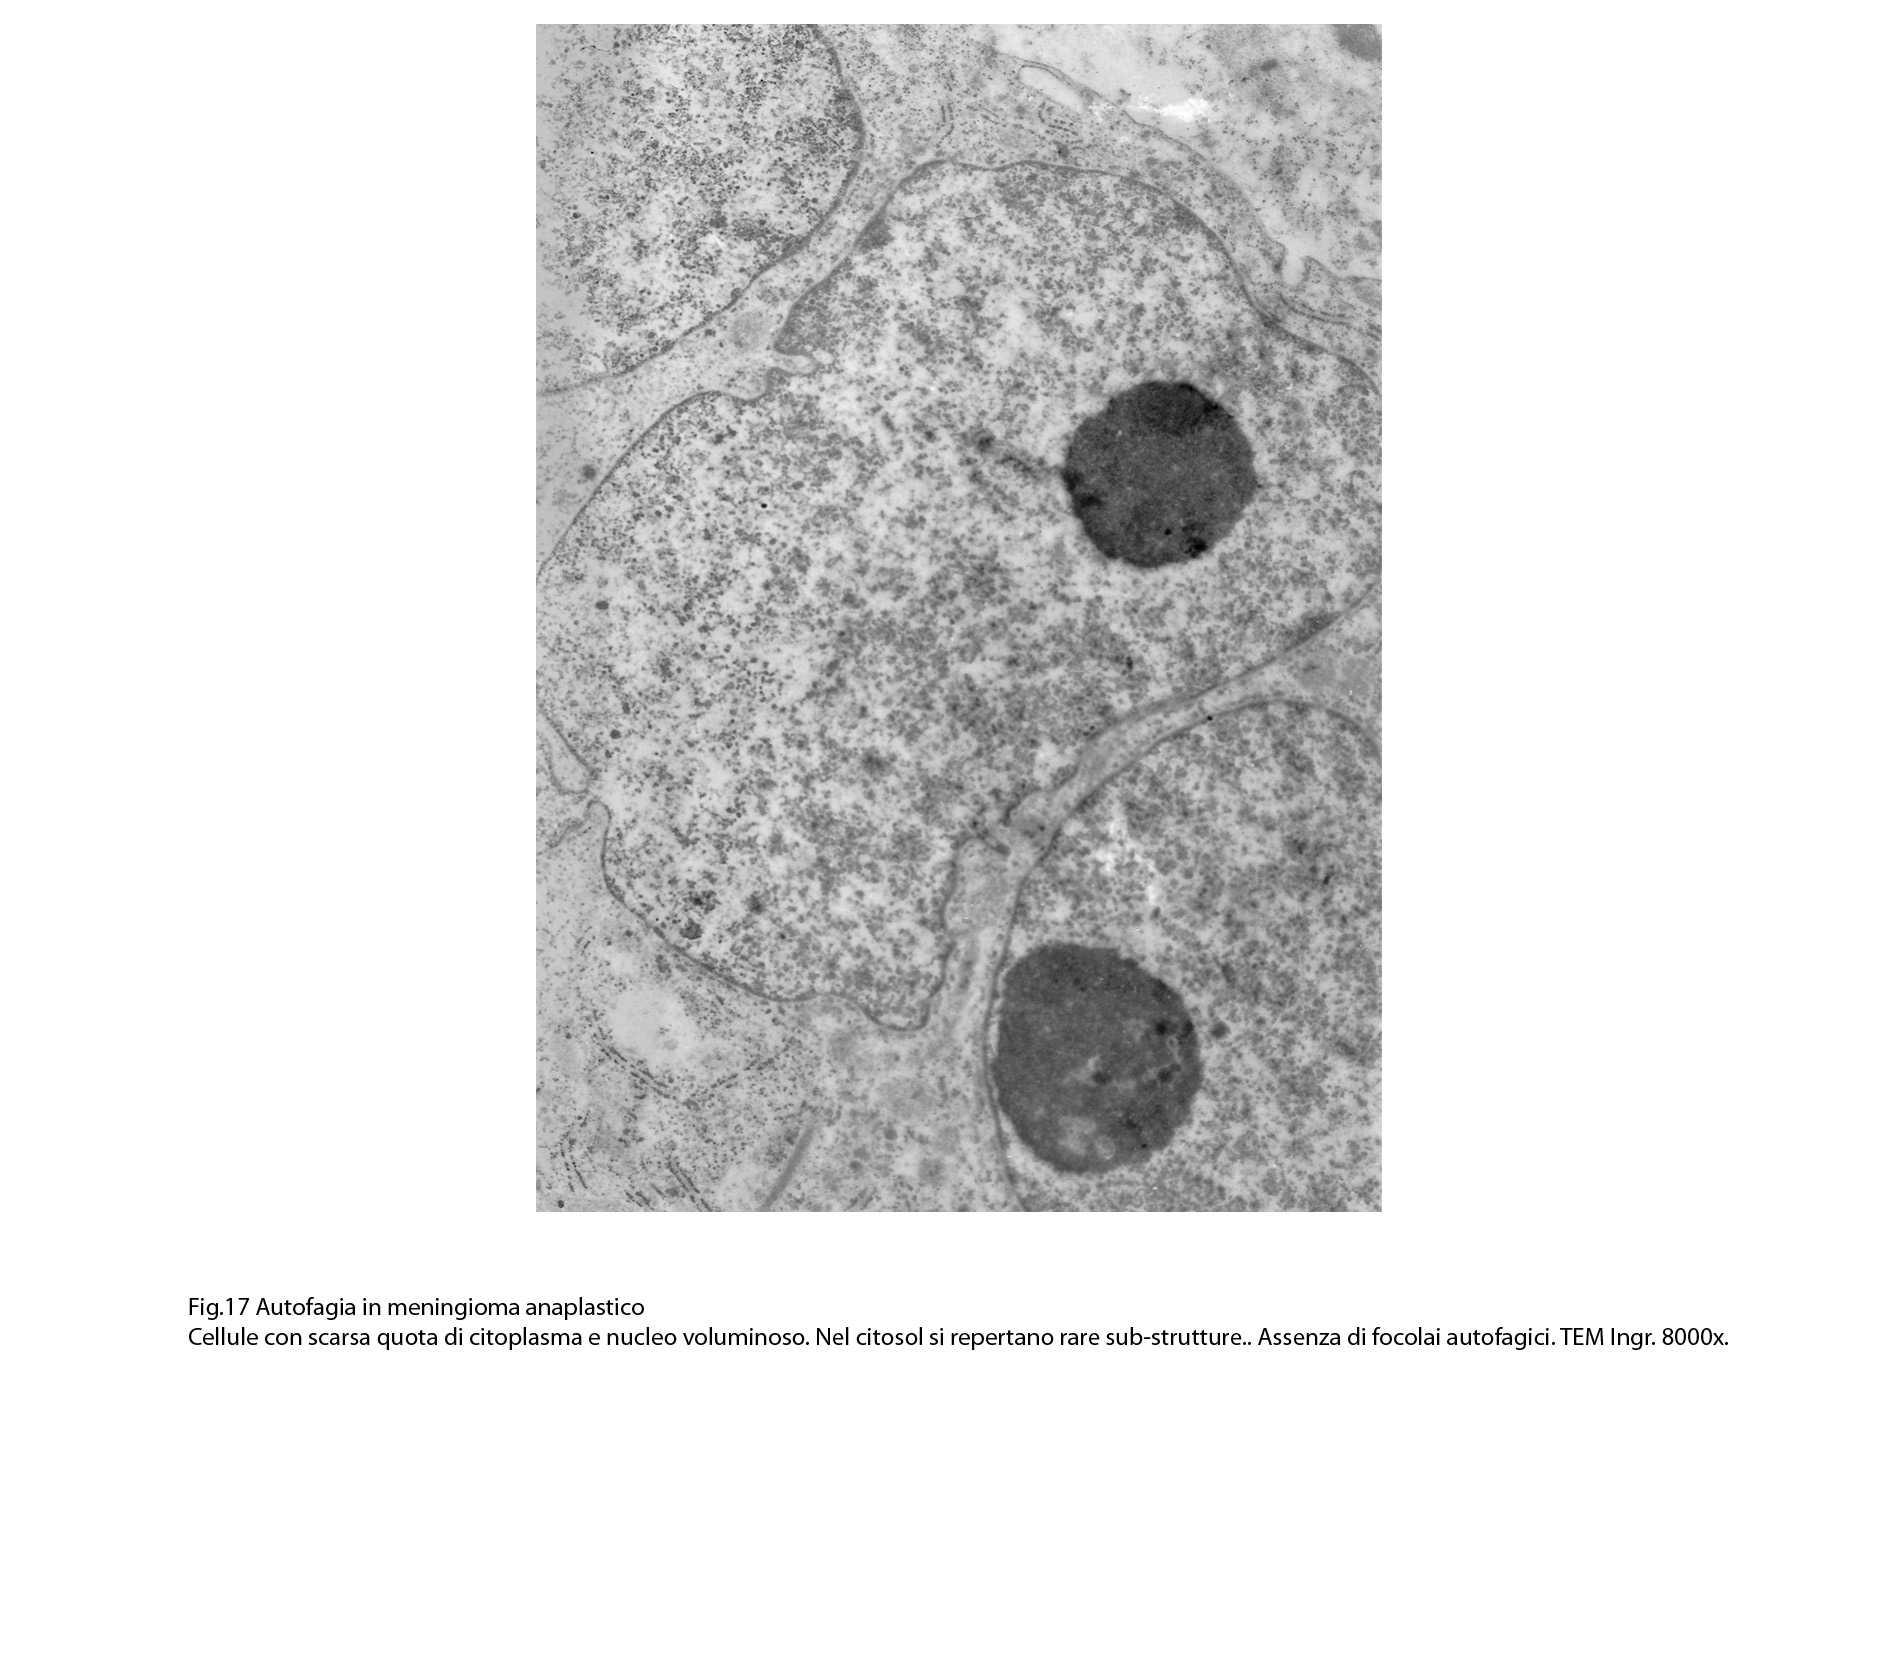

B) FOCOLAI DI AUTOFAGIA IN MENINGIOMI ANAPLASTICI

La popolazione cellulare dei meningiomi anaplastici è data da elementi di piccole e medie dimensioni che si dispongono spazialmente in aggregati informi. Ciascuno di essi ha una forma irregolarmente cuboide o poligonale e soprattutto è caratterizzato da una esigua quota citoplasmatica esigua e da una voluminosa massa nucleare.

Al microscopio elettronico,il citoplasma appare compatto ed il citosol contiene pochi mitocondri, scarso reticolo endoplasmatico ed ergastoplasma, discrete quote di ribosomi liberi e di microtubuli.

Molto frequentemente si riscontrano elementi i quali evidenziano una condizione di cellula binucleata.

Le numerose osservazioni ultrastrutturali condotte su casi di meningiomi anaplastici hanno evidenziato in modo ripetitivo gli abituali caratteri di cellule con tale morfologia e in nessun campo hanno evidenziato focolai riferibili a processi di autofagia.